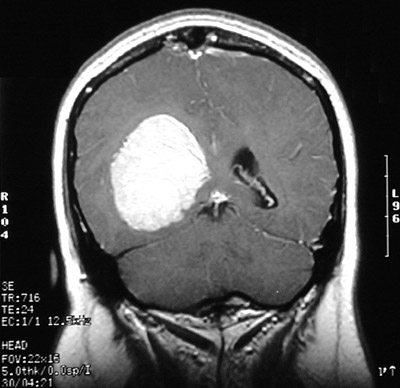

| The T1 weighted MRI scan in axial view above demonstrates another less common location for a meningioma, an intraventricular meningioma. In this location, a circumscribed mass could also be an ependymoma. Below can be seen the same right lateral ventricular mass with contrast enhancement in T2 weighted axial view and T1 weighted coronal view. |